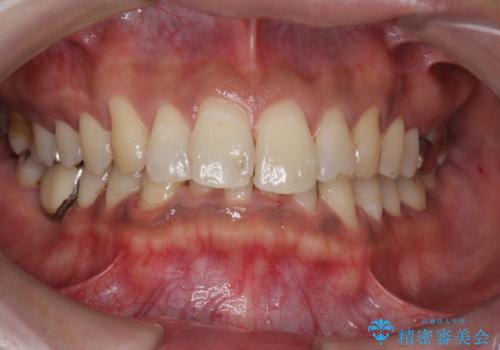

タバコによるヤニ、着色、歯の汚れをPMTC(60分コース)で除去。